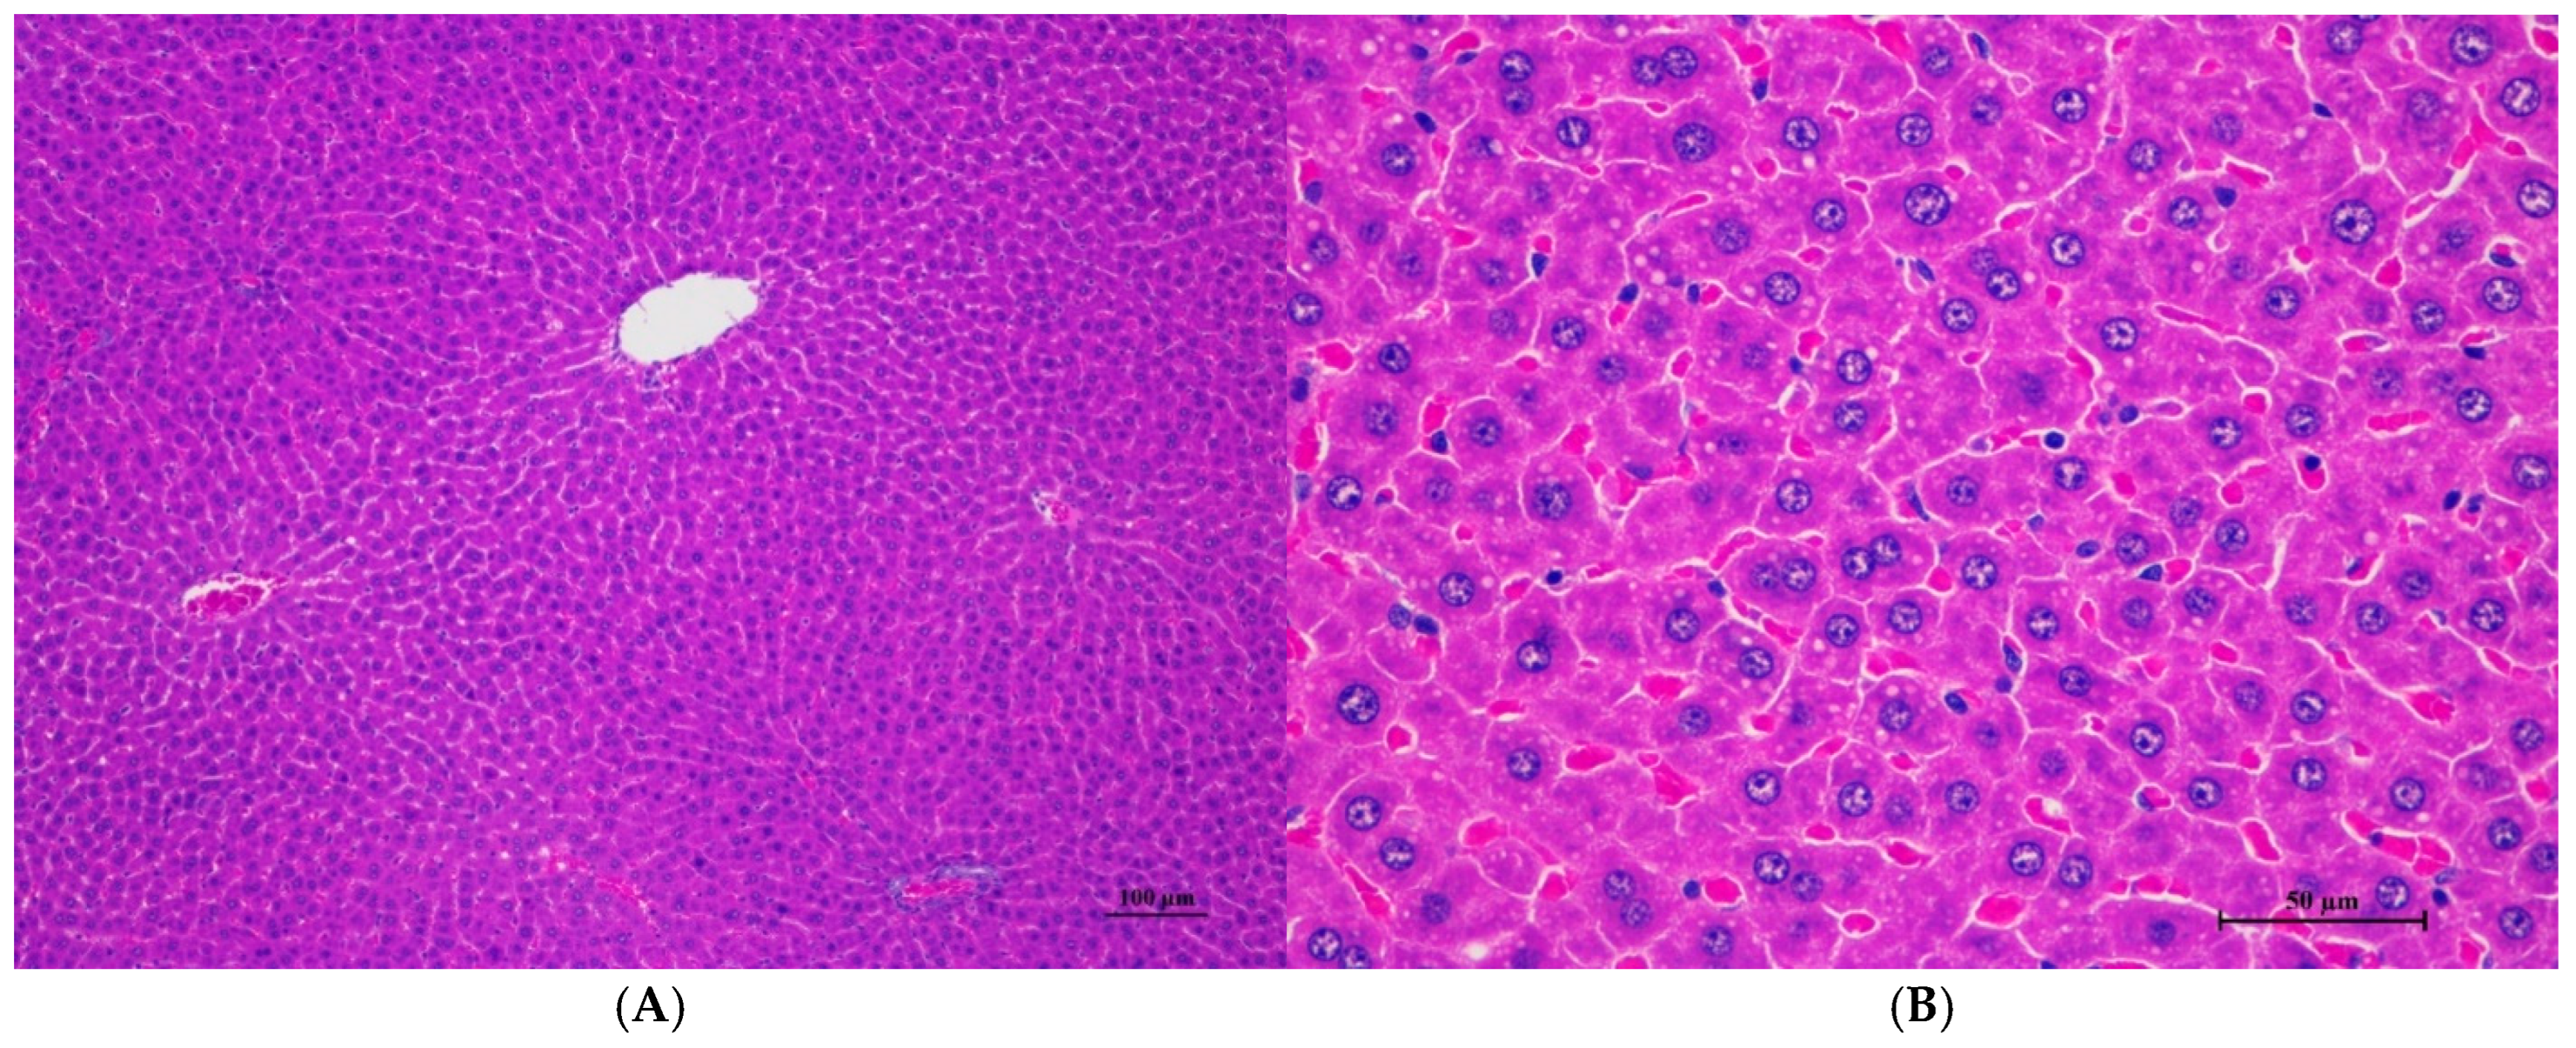

Figure 6.

Histopathological examination of rat liver tissue in sub-acute toxicity from daily (28 days) fed oral dose of CDF revealed infrequent findings and no prominent lesions. (A) The liver tissue showed an intact lobular arrangement of the hepatic cord and central vein (100×, H&E). (B) High magnification showed structurally normal hepatocytes with distinct cellular boundaries and centrally located nuclei. Occasional hepatocytes contained fine cytoplasmic vacuolation (400×, H&E).

Histopathological analysis of rat organs following 28-day cassava fiber administration revealed mild hepatocellular swelling and vacuolation in the liver, deemed within normal limits, while the kidneys, heart, and spleen exhibited no significant lesions; however, the lungs consistently displayed moderate to severe alveolar edema, septal engorgement, hemorrhage, and inflammatory cell infiltration, suggesting a potential pulmonary response to the cassava fiber, despite the absence of overt clinical toxicity.

Rats of both sexes, with respect to histopathological changes in the liver, kidney, heart, and spleen, were normal. Histopathological changes in the liver, including hepatic vacuolation and hepatic degeneration, were found in all groups of both sexes. These changes were found to be abnormal in the cytoplasm of liver cells, to a mild degree and diffuse in some areas of the liver, and portal tracts were normal. These findings represent only minimal and non-significant pathologic changes. Additionally, biochemical values were within normal limits, indicating this organ remained normal.